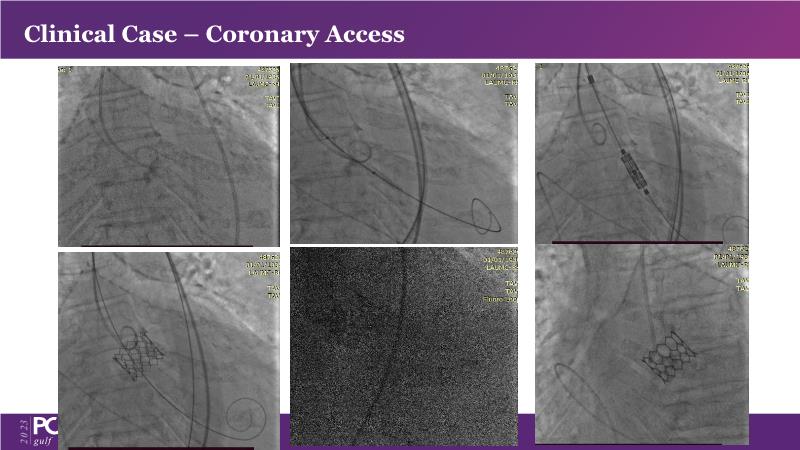

This session is a valuable resource for grasping innovative strategies in handling bifurcation and extended diffuse lesions through dedicated stenting solutions. Explore insights into the advanced Myval next-generation THV technology, unveiling its distinctive features, procedural advantages, and clinical outcomes across a diverse patient pool. Gain understanding into the CorAlign technique, ensuring accurate commissural and coronary alignment while maintaining coronary access. Additionally, delve into the techniques for precise sizing, positioning, and deploying of Myval THV.

- To understand the CorAlign technique which enables predictable and precise commissural and coronary alignment thus preserving coronary access